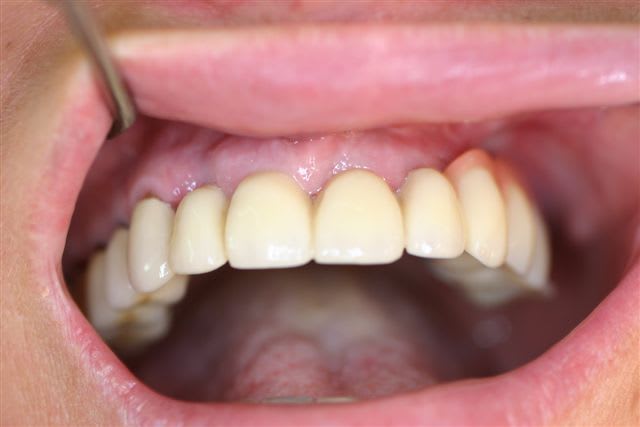

Voici le modèle stéréolithographique et la apno post op

Pépé